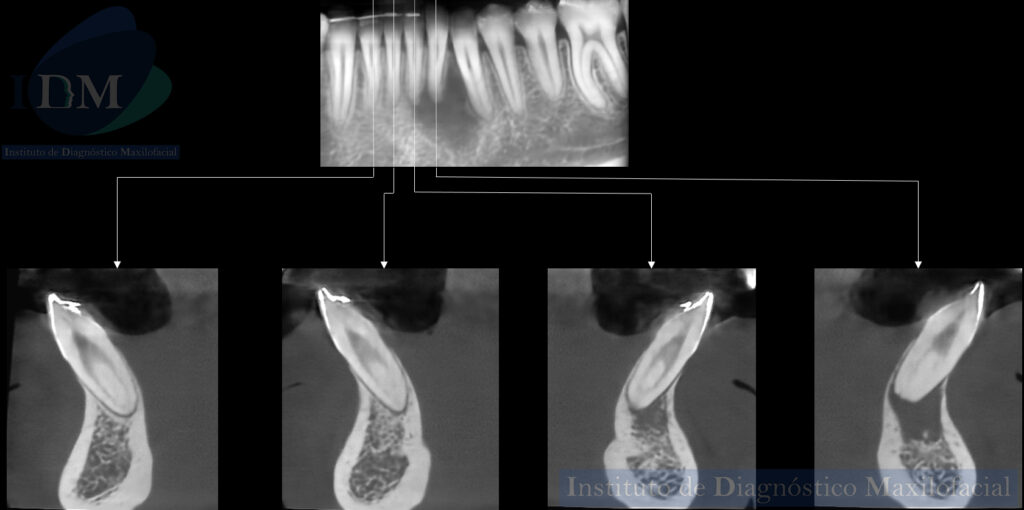

A la evaluación de la tomografía volumétrica (CBCT) en los cortes axiales (Figura 2) y transaxiales (Figura 3), se aprecia proceso osteolítico periapical en pieza 32 que ocasiona el borramiento parcial de la lámina dura de piezas 33 y 31, a la vez se evidencia presencia de dos conductos a nivel de tercio cervical y medio que convergen a nivel apical en piezas 32, 31, 41, 42.

En las reconstrucciones 3D se representa la presencia de dos conductos radiculares en piezas anteriores del maxilar inferior. (Figura 4).

CORTES TRANSAXIALES

RECONSTRUCCIÓN 3D